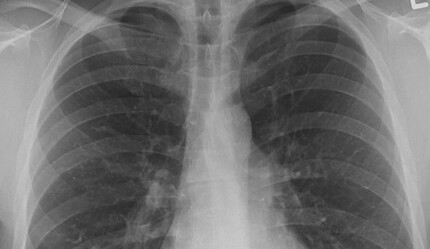

Genellikle kış aylarında yaygın olan üst solunum yolu hastalıkları sağlığı tehdit etmeye başladı. Yakın geçmişte tüm dünyayı etkisi altına alan Covid-19 pandemisi ile salgınla yaşamayı öğrensek de yeni virüs ve salgınlar ortaya çıkıyor. Covid-19, grip ve RSV'nin bir araya gelmesiyle ortaya çıkan “üçlü salgın” tehlikesi ile karşı karşıyayız. Özellikle RSV, küçük yaş gruplarında, yaşlılarda ve bağışıklığı düşük bireylerde daha ağır ilerliyor.